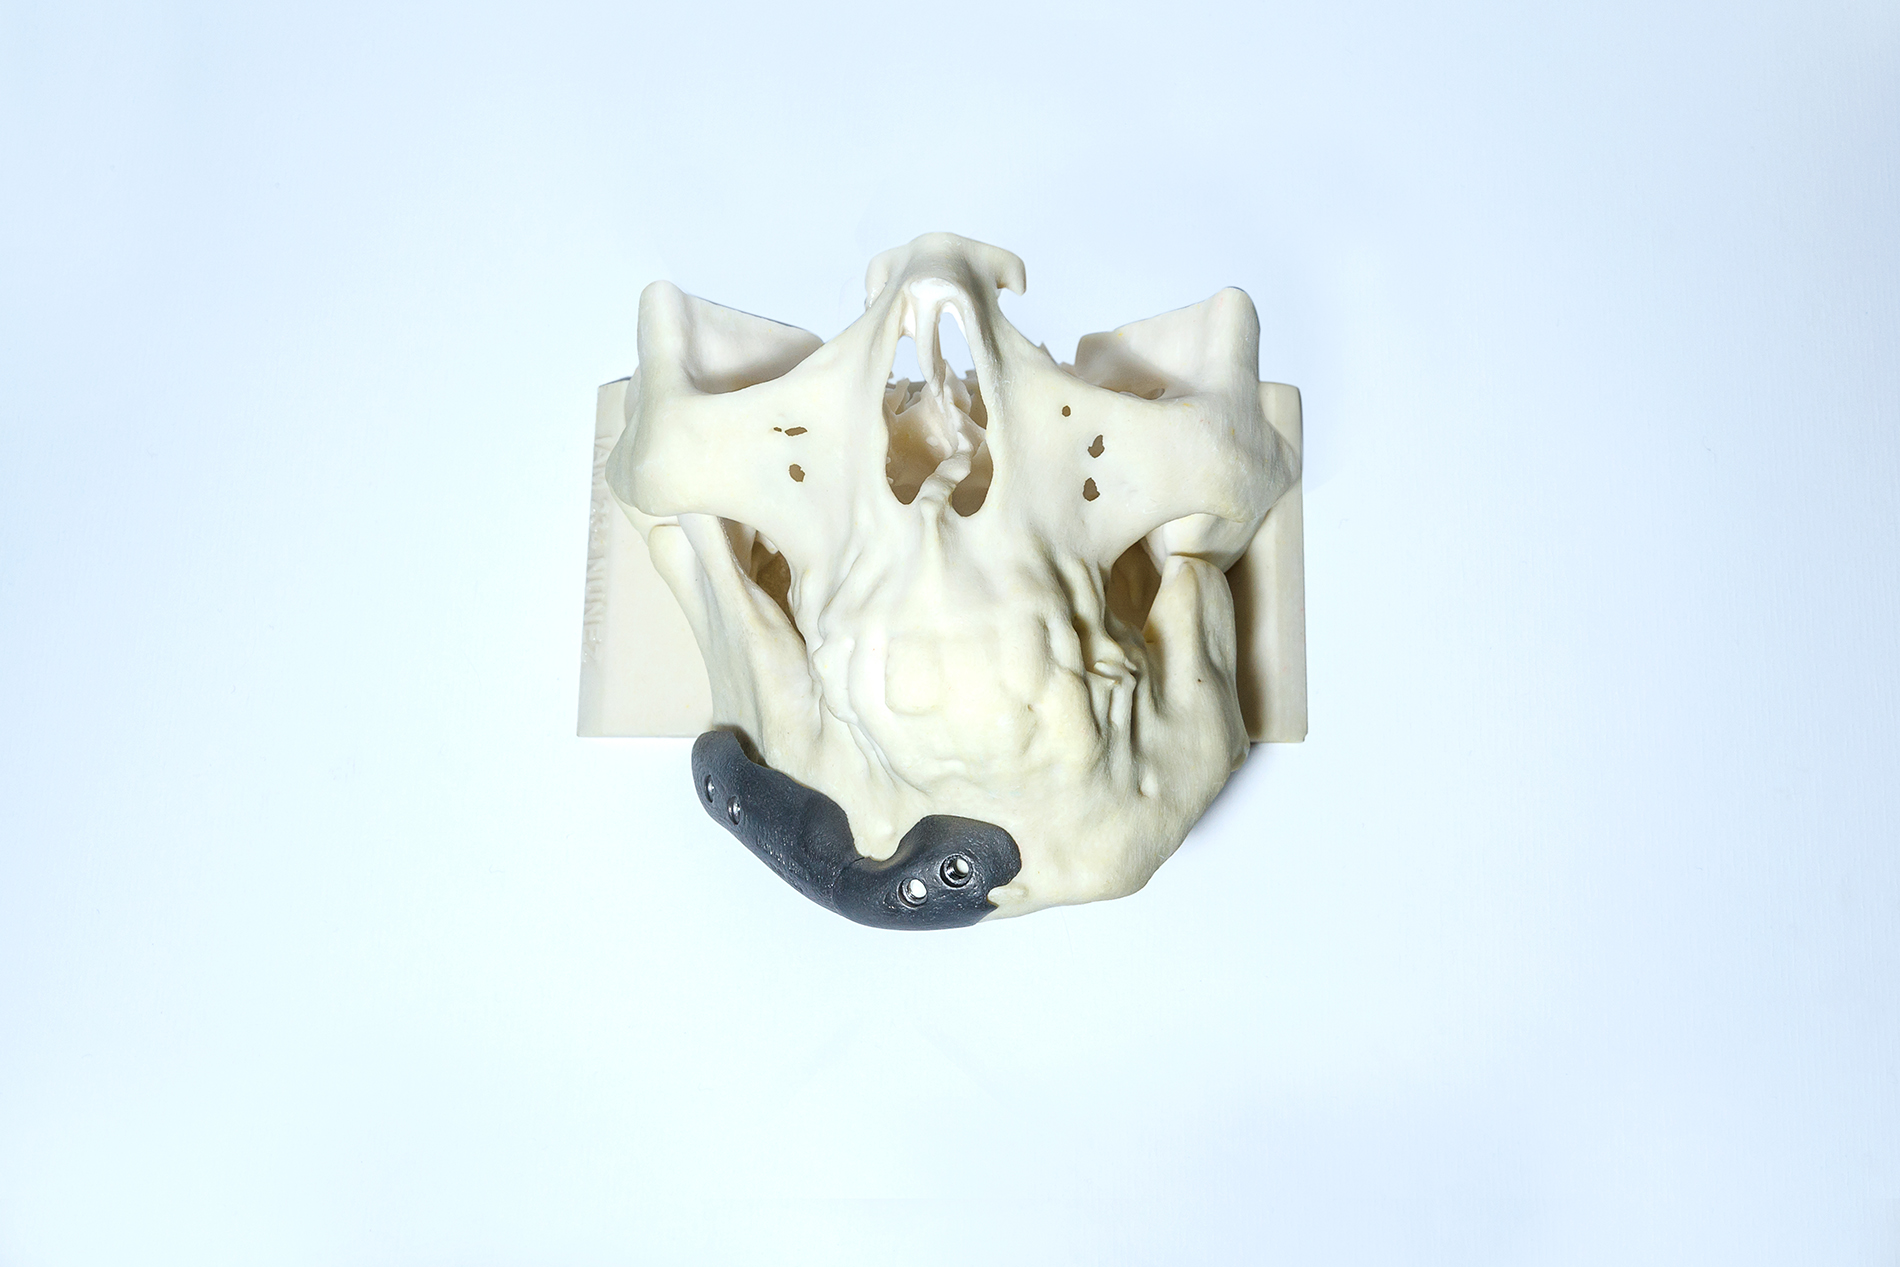

La reconstrucción utiliza como información de entrada imágenes obtenidas por técnicas de diagnóstico (TAC o MRI). A través de un software especializado se procesan las imágenes y se logra modelar en tres dimensiones cualquier región anatómica con patologías diversas.

En el modelado 3D digital se pueden incluir implantes ortopédicos como placas, tornillos, mallas, prótesis, etc., y también modelados en 3D y en tamaño real en relación con el modelo anatómico. De esta forma es posible simular diferentes situaciones con las que el cirujano se enfrentará durante el proceso quirúrgico.

El prototipo plástico se consigue a partir de la realización de un modelado digital 3D. La pieza obtenida respeta las medidas de la anatomía, pudiendo el cirujano, de esta manera, tener una idea real de la patología a tratar.

Una vez obtenida la información de la TAC o MRI y modelado el 3D digital, podemos modelar la prótesis que se necesita (por ejemplo, una porción de calota faltante) y posteriormente realizarla en resina plástica. De esta manera validamos la adaptación del futuro implante a la anatomía. El cirujano puede verificar las imágenes modeladas digitalmente o el prototipo en resina plástica, y sugerir modificaciones dando paso al proceso final.

Antes de la fabricación del implante, el cirujano puede elegir entre dos métodos de examen del implante PROTOLAB: 1) Un modelo del cráneo y del implante para ser examinado, marcado o aprobado;